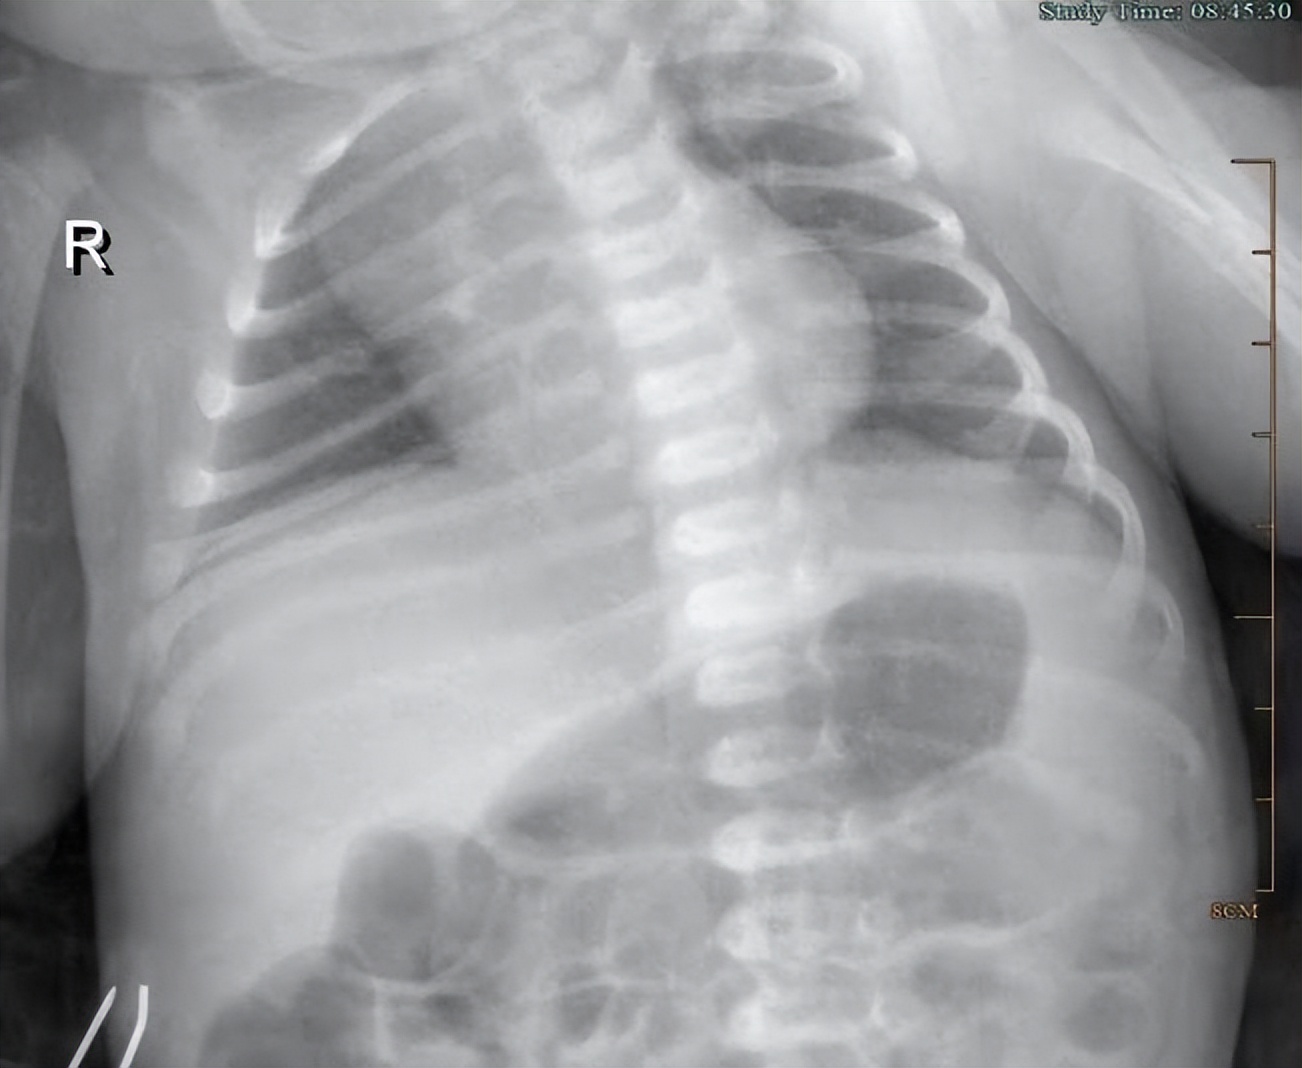

患儿入院后,基于“新生儿肺炎”的考虑,进一步完善胸片,血常规+CRP,血凝常规,血型检测,血气分析,尿常规,肝功肾功等相关检查。这些检查是为了进一步确诊患儿是否是新生儿肺炎,从而排除其他误诊。检查结果示患儿双肺有弥漫性、深浅不一的模糊影,白细胞明显增多,达21.9*10^9/L,血红蛋白增多,CRP全血快速定量增多,3.62mg/L,血型Rh阳性,血型为AB型,尿比重 1.008,红细胞9/ul,白细胞 52/ul,总胆红素100.90μmol/L,直接胆红素 10.4μmol/L,间接胆红素 90.5μmol/L,偏高。

经过住院治疗后,患儿呼吸道通畅,睡眠佳,精神状态可,复查血常规,白细胞恢复正常,胸片恢复正常。

经住院治疗6天,患儿包被保暖,无发热或体温不升,大气吸入下经皮氧饱和度维持在95%以上,无气促、*吟呻**,无呼吸暂停,无少吃、少哭、少动,无激惹,无尖叫、抽搐,奶口服,奶量完成可,无呕吐,无腹胀。大小便无殊。今晨经皮胆红素测定9.4mg/dl。进一步复查患者白细胞恢复正常,胸片恢复正常。查体咽无充血,双肺呼吸音粗,未见明显干湿啰音。